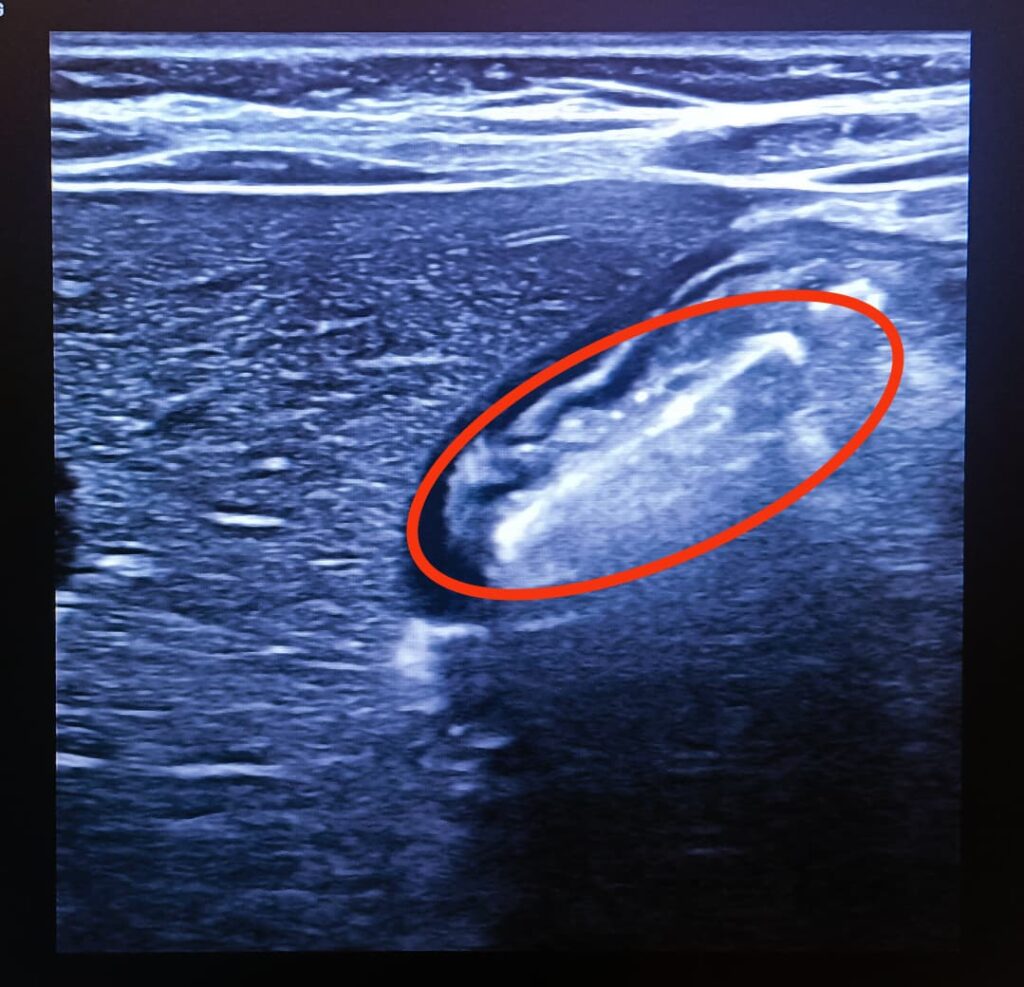

The battery was localized in the pylorus of the stomach, just proximal to the first part of the duodenum.

The ultrasound image demonstrating the foreign body is as appended below.